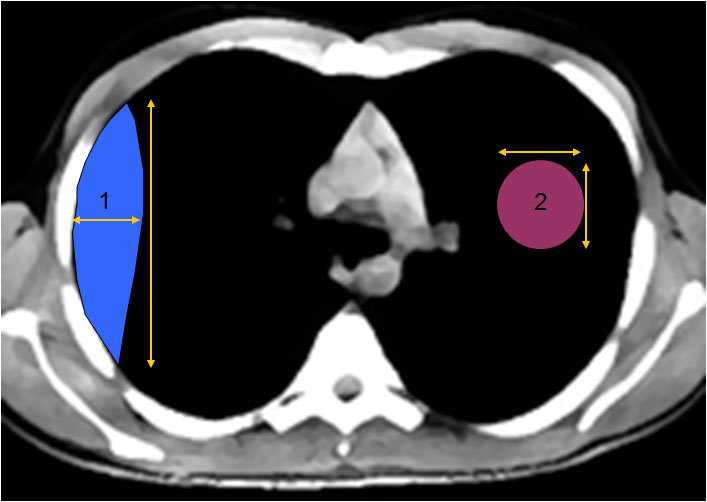

SIGNO DE DISCORDANCIA DEL NIVEL HIDROAÉREO

La diferente densidad y longitud del nivel hidroaéreo de una colección intratorácica en las proyecciones PA y L de tórax , es un signo de derrame encapsulado pleural, que permite diferenciarlo de cavidades de localización intrapulmonar (absceso, quiste, tumor cavitado, etc.). Cuando el encapsulado es de localización posterior o anterior, en la proyección PA el nivel aparece largo y de baja densidad radiológica, mientras que en la lateral el nivel es corto y más denso. Los mismos hallazgos, aunque a la inversa, ocurren cuando el encapsulado es de localización lateral o medial.

Esquema de crecimiento de las colecciones extrapulmoanres (1) frente a las intrapulmonares (2). La morfología de las primeras justifica la diferencia de tamaño de un nivel hidroaéreo –cuando lo hay-. En cambio, en los abscesos y otras lesiones intrapulmonares, el nivel hidroaéreo tiene una longitud similar en las dos proyecciones.

(Las causas de la presencia de aire en un derrame encapsulado son: la fístula broncopleural, la introducción del aire tras la aspiración del líquido pleural, la infección por gérmenes productores de gas y el traumatismo espontáneo o quirúrgico).